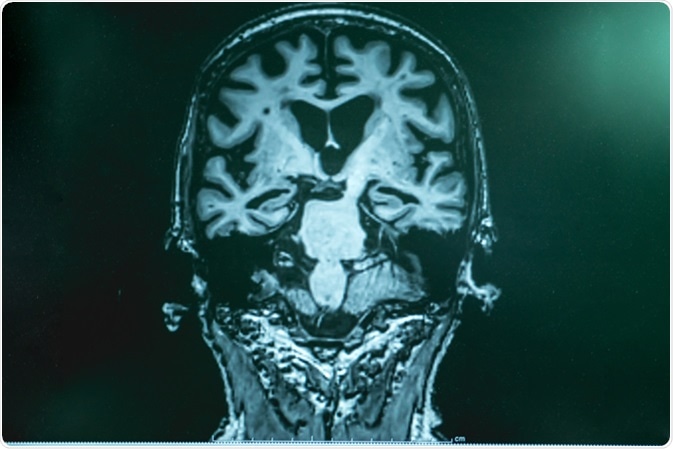

Alzheimer

Alzheimer's disease with MRI. Image Credit: Atthapon Raksthaput / Shutterstock

Clinical methods that are also useful in diagnosing dementia include cognitive and neuropsychological tests; laboratory examinations of blood or other body fluids for the detection of hormones, vitamins, and other biochemical parameters; brain scans such as CT, MRI, and PET to detect stroke and other related vascular injuries; psychiatric assessment to detect mental health condition; and genetic tests to detect genetic risk factors related to dementia.